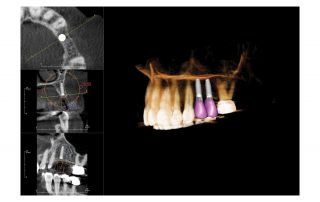

Four defined volume sizes